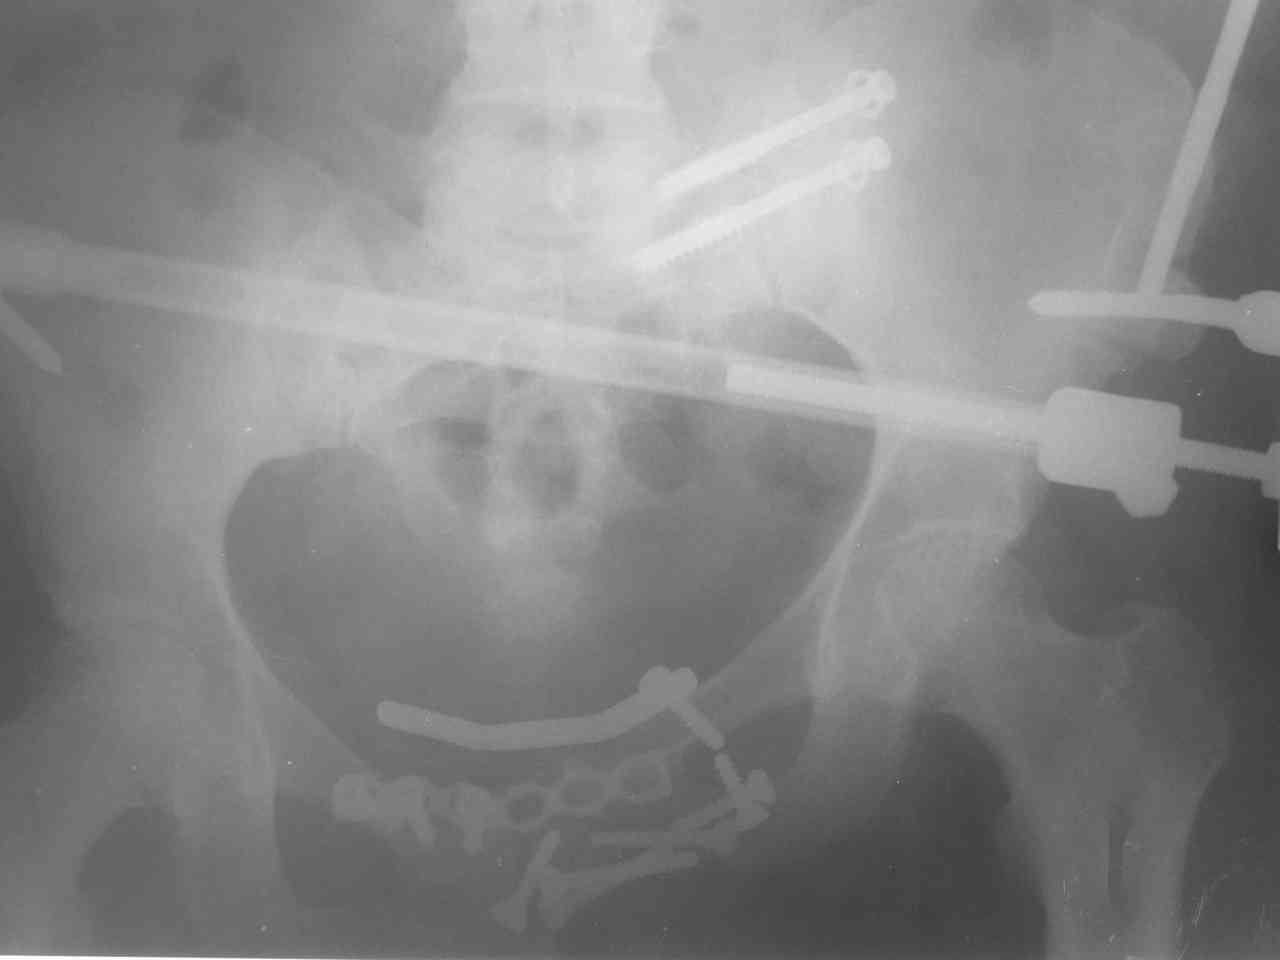

Уважаемый Алексей, основная ошибка - короткие илиосакральные винты. Без надежной фиксации крестца передние конструкции не удержатся (Если только больную на вытяжение не положить).

1. Повторить ту же процедуру, но увеличить длину илиосакральных винтов до контрлатеральной массы крестца, швейцарская реконструкционная пластина на 8 отверстий по верхней поверхности с 3,5мм винтами через оба кортикала, особенно в теле лонных костей. Аппарат в существующем виде большой пользы не принесет, однако, если страшно, можно его оставить но многократно усилить (сделать кольцевым, захватить надвертлужную область, задние ости, добавить стержней в крылья)

Алексей спасибо за советы. Привет. Не секрет. Мы в Хабаровске. При первом вмешательстве сначала шли сзади - рубцы убирали, затем спереди и после

синтеза 2-мя пластинами 10 винтов делали костную пластику в области лона.

Сегодня оперировали больную повторно. Начали сзади. Винты сменили на три + пластина на 8 винтов - крестец- подвздошная кость. Осталось до 1 см смещения кверху- но рассчитываем на анкилоз сзади. После этого пошли кпереди - убрали весь металл и сменили на пластину 8 винтов и пластину 6 винтов + костный трансплантат в лоно для замыкания таза. После чего решили апппарат не накладывать (уже было два) а дисциплинарное вытяжение на 6 недель. К сожалению пациентка курилка - и помчалась после первой операции в курилку - на 3 - неделе упала поскользнувшись на кофе. Неврологический дефицит есть, в виде нарушений чувствительности типа нейропраксии, но он был и до первого

вмешательства и не нарос после второго. Пациентка за 50 и полновата.